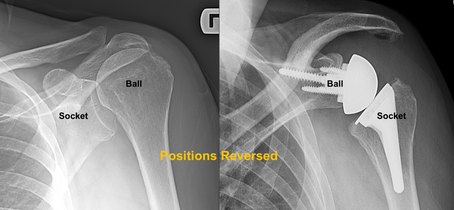

Reverse Shoulder Replacement

Persistent shoulder pain and weakness can severely limit daily activities. Reverse Shoulder Arthroplasty is a modern surgical solution designed for patients with rotator cuff tear arthropathy, complex fractures, or failed shoulder surgeries, offering reliable pain relief and improved shoulder function.